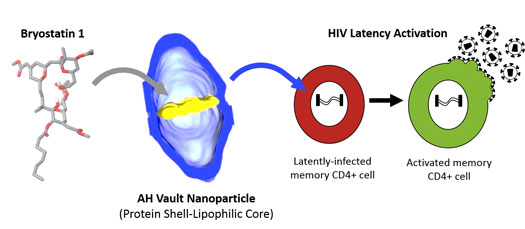

The research of drug therapies to HIV patients through the use of nanotechnology.

New research led by the University of Liverpool aims to improve the administration and availability of drug therapies to HIV patients through the use of nanot…